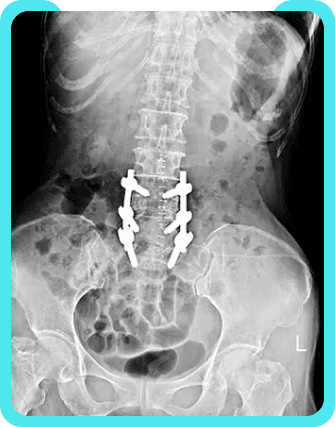

Typically, the nature of the pain experienced by patients with post-laminectomy syndrome correlates with the underlying pathology. One type of post laminectomy pain is neuropathic pain, which is caused initially by primary injury to the nervous system. In patients with post-laminectomy syndrome, the original spinal disorder that caused the nerve injury prior to surgery may cause neuropathic pain to return. Another type of pain that may persist after back surgery is radicular pain, or shooting pain that travels along the dermatome or sensory distribution of a nerve due to inflammation or other irritation of the nerve root. Initially, nerve root irritation may arise from a spinal disc herniation, or torn or bulging disc. Eventually, neuropathic and radicular pain can result in central sensitization of nervous tissues, or harmful changes to pain receptors. Treatments for this syndrome can range from medication and physical therapy, and even additional surgery if the pain is too great. It is crucial to seek a pain management doctor because an accurate diagnosis is imperative. A precise diagnosis is necessary to facilitate an effective plan of treatment. An evaluation may include x-rays, MRIs, EMGs, and other means of identification. After identifying the source of your ailment, a treatment plan can be prescribed and implemented.